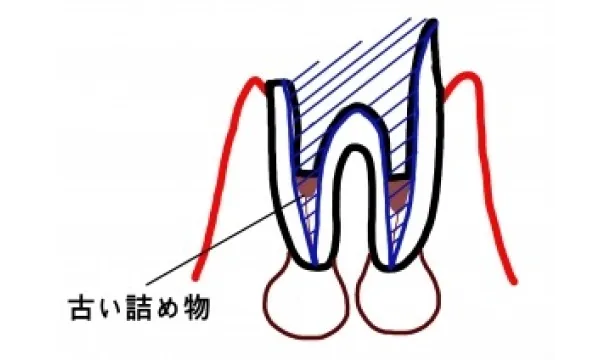

根の治療のやり直しの場合

根の治療のうち過去に根の治療をして神経はないが痛みがある、あるいは化膿して膿が出ていたり腫れている場合の治療手順をご説明します。 根の治療のやり直しの問題点は、本来の神経入っていたトンネルが、ふさがっていたり道がそれていることがあることです。当然、神経をとる根の治療より難易度が上がります。また、非常に炎症が強い場合はすぐに根の治療を始められないことがあります。この場合は、一時的に薬を飲んでもらったり、切開して膿を出したりして炎症を弱める治療をまずする必要があります。 やり直し治療の手順は、まずついているかぶせものや土台をとります。当然とれないようについているのでとるには時間がかかり、歯質は極力削れないようにするので顕微鏡を使って慎重に削っていきます。

すると、根の中の詰め物が見えてきます。この古い根中の詰め物(多くはゴムや練り薬、まれに根の治療器具など)を取り、腐敗した残存物を取り除きます。トンネルの開通や修正を行い、根の先まで長さを慎重に測り、清掃する長さを決定し、その位置まで清掃、拡大を行います。 清掃は、器具によって機械的にトンネルを拡大するのと薬物によって化学的に拡大します。薬を使って安静と再感染を防ぎ炎症が消退したら根の中に滅菌されたゴムを圧力をかけてつめ根の治療を終わります。